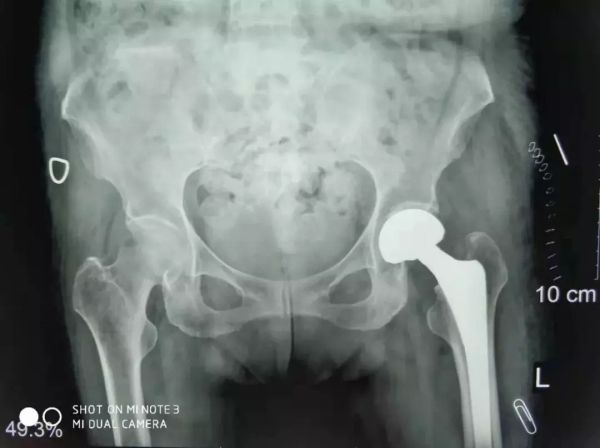

關(guān)節(jié)科羅軍主任和易觀俊主治醫(yī)師聯(lián)合麻醉科、內(nèi)科、超聲科專家集體會(huì)診及評(píng)估,并確定了最佳手術(shù)方式和麻醉方案,并積極做好充分的術(shù)前準(zhǔn)備。于是,11月2日在危立軍副院長(zhǎng)帶領(lǐng)手術(shù)團(tuán)隊(duì)按照術(shù)前的討論方案,在腰部麻醉下行人工股骨頭置換,手術(shù)僅用了20分鐘。

患者股骨頭置換手術(shù)照片